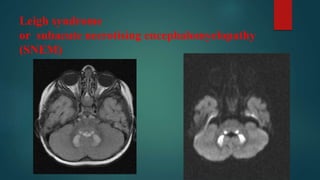

Leigh syndrome

or subacute necrotising encephalomyelopathy

(SNEM)

• #53 Diffuse T2 hyperintensities and restricted DWI signal of the pons with extension into the middle cerebellar peduncles. Also similar increased T2 signal of the symmetric basal ganglia, including the caudate nuclei, putamina, as well as the ventrolateral thalami, without the restriction of diffusion. 2. On MRI images seen T2, FLAIR hyperintensity in medulla oblangata, pons, both thalami and putamen, and the caudate nuclei.  Additionally an cavum septum pellucidum and cavum vergae.

• #54 There is symmetric marked hyperintense signal intensity on T2/FLAIR imaging and restricted diffusion in the dentate nuclei, inferior cerebellar peduncles, lateral fourth ventricle floor in the expected locations of the vestibular tract and in the expected tract of the vestibular cochlear nerve. Also present, is diffusion restriction in the posterior columns of the proximal cervical cord, anteriorly in the inferior medulla, and punctate symmetric foci of restricted diffusion in the inferior colliculi of the quadrigeminal plate and medial geniculate bodies. There is mild high signal on FLAIR and diffusion weighted imaging involving the bilateral putamen 2nd image is dwi image